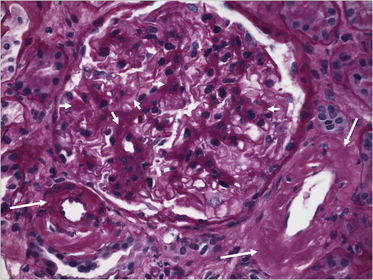

TISSUE TYPE: glomeruli... kidney PATHOLOGY: depsition of foreign material in wall of capillaries .. DIAGNOSIS: Amyliodosis ( can be found in tubules ... afferent arterioles or in interlobular a.) N.B: Amyloidosis in kidney... sarcoidosis in lymph nodes..